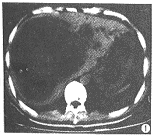

CT示:肝内见一巨大类圆形肿块,直径大小约16.5cm,边界尚清晰。其内以囊性为主,囊壁有乳头状实性突起及少量实性分隔(图1)。增强扫描见纤维间隔有强化(图2)。

图1 肝内一巨大类圆形肿块,边界尚清晰,其内以囊性为主,囊壁有乳头状突起及少量实性分隔